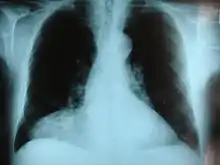

| Morgagni hernia seen on a chest radiograph. | |